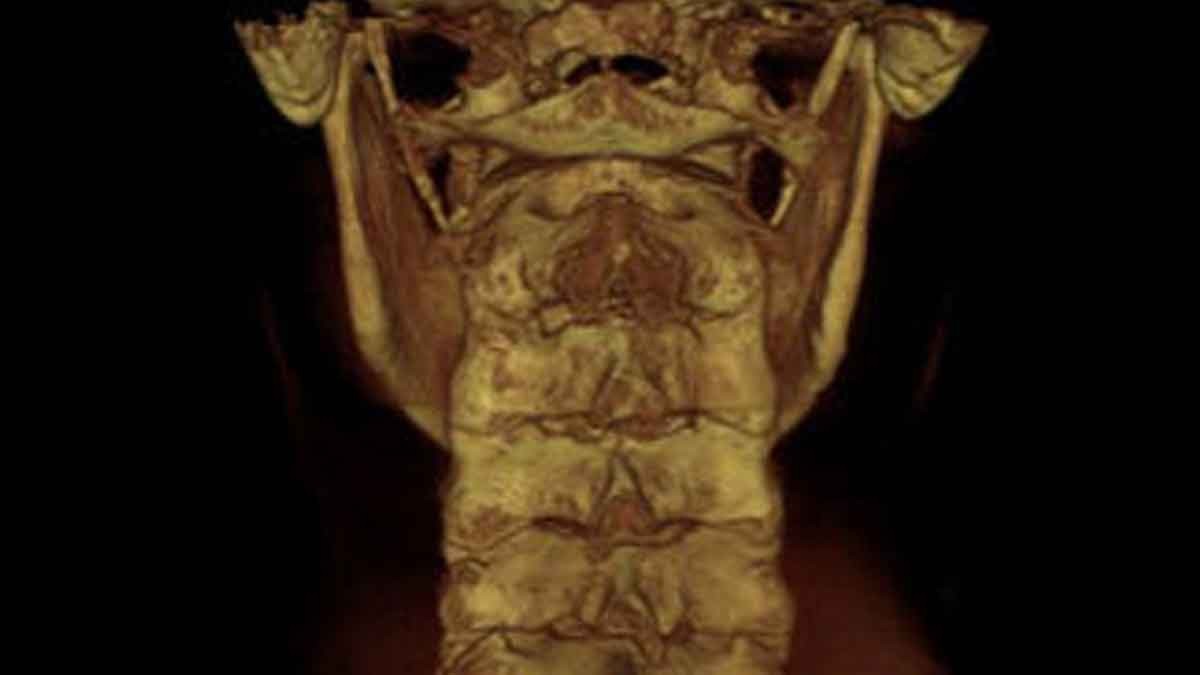

AXIAL VIEW OF FORAMEN MAGNUM AND ATLAS

This view allows the doctor to study the alignment of the upper cervical spine in a traditional APOM view. In chiropractic, the APOM is viewed from the posterior to the anterior to keep left and right right.